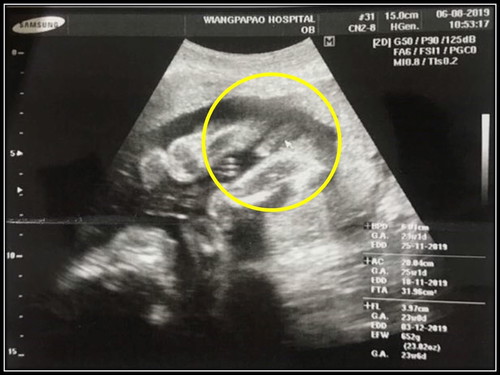

ตื่นเต้น ได้ลูกผู้ชายค่ะหลังจากหนีบไว้ จนถึง 24 Weeks